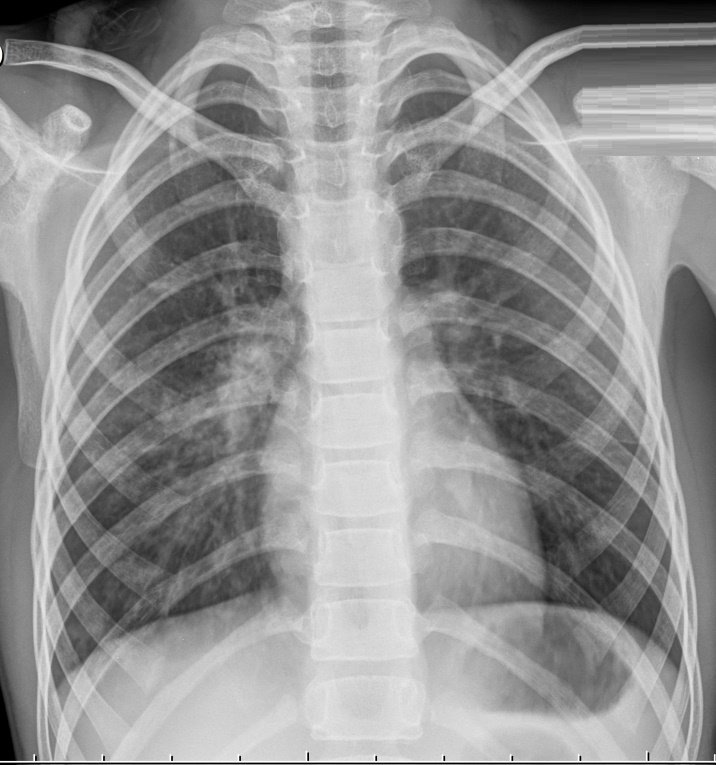

Крупозная пневмония – гиперергическое воспаление, которое проходит следующие стадии: прилив, красное и серое опеченение и период разрешения.

На снимках видно, что воспалительный процесс локализуется лобарно или сублобарно (то есть поражается доля легкого) с вовлечением плевры. Легочный рисунок при этом изменяется, а легочные корни расширяются. Видны застои жидкости в плевральной полости. С течением болезни тени на снимках становятся темнее.

Крупозная пневмония